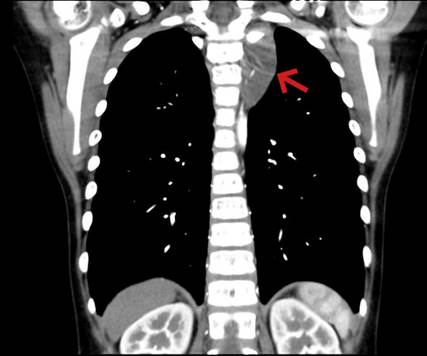

一一(化名)是一个8岁的男孩,从小开始一侧面部和对侧躯干就出汗少,家长未重视。2个月前左侧胸部出现针刺样疼痛,休息后疼痛会缓解。1周前因流行性感冒到我院呼吸科门诊,胸部CT检查发现左侧纵膈内有一肿瘤,大小和鸡蛋差不多。呼吸科医生嘱托转心胸外科就诊,我科收治入院后完善一系列检查,考虑是神经来源肿瘤,明确了肿瘤位置在左侧后上纵膈胸椎旁。经过术前仔细的读片,发现肿瘤已经往椎间孔里生长,虽然还没有侵犯到脊髓,但是完整切除不仅难度大、而且容易损伤脊髓神经,也容易有肿瘤的残留导致术后复发术前血液科会诊,完善相关检查均未能明确肿瘤病理性质,须手术治疗。

(箭头所示为长入椎间孔之纵隔肿瘤)